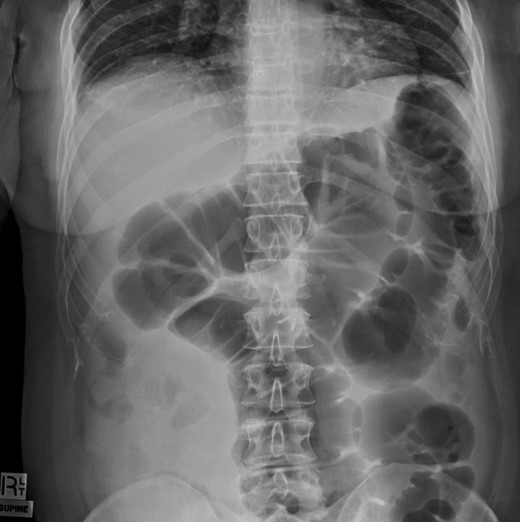

Colonoscopy revealed melanosis coli, diverticulosis and grade four hemorrhoids. She was admitted overnight following haemorrhoidectomy. The following morning she complained of abdominal pain, which she described similar to diverticulitis, and she was tender on exam. To rule out perforation, a plain film abdomen was performed. Findings were suggestive of gaseous distension following colonoscopic air insufflation without evidence of free gas (Fig. 1). Watchful waiting approach was adopted, however the patient deteriorated further during the course of the day. She had a vasovagal episode with tachycardia (134 bpm) and hypotension (67/47 mmHg). A venous blood gas revealed lactate level of 7 mmol/l. She underwent an urgent CT with findings suggestive of pericaecal internal hernia with the ileal loops located in the right paracolic gutter demonstrating features of ischemia (Fig. 2). There was moderate amount of free fluid, but no free gas to suggest perforation (Fig. 3). She was taken to theater that day for emergency laparotomy. The intraoperative findings included two litres of bloodstained fluid and floppy cecum with a band of adhesion to its own mesenteric base, probably adhesional having developed after the appendicectomy. This band has created a window through which three quarters of her small bowel had herniated and became strangulated. The bowel looked very ischemic, but not necrosed. The surgeons divided the adhesion, untwisted the small bowel and waited 20 minutes to allow sufficient time for bowel ischemia to recover. Fortunately, she did not require any bowel resection.

CT axial view showing dilated colon, internal hernia with ischemic small bowel loops, free fluid, but no free gas.